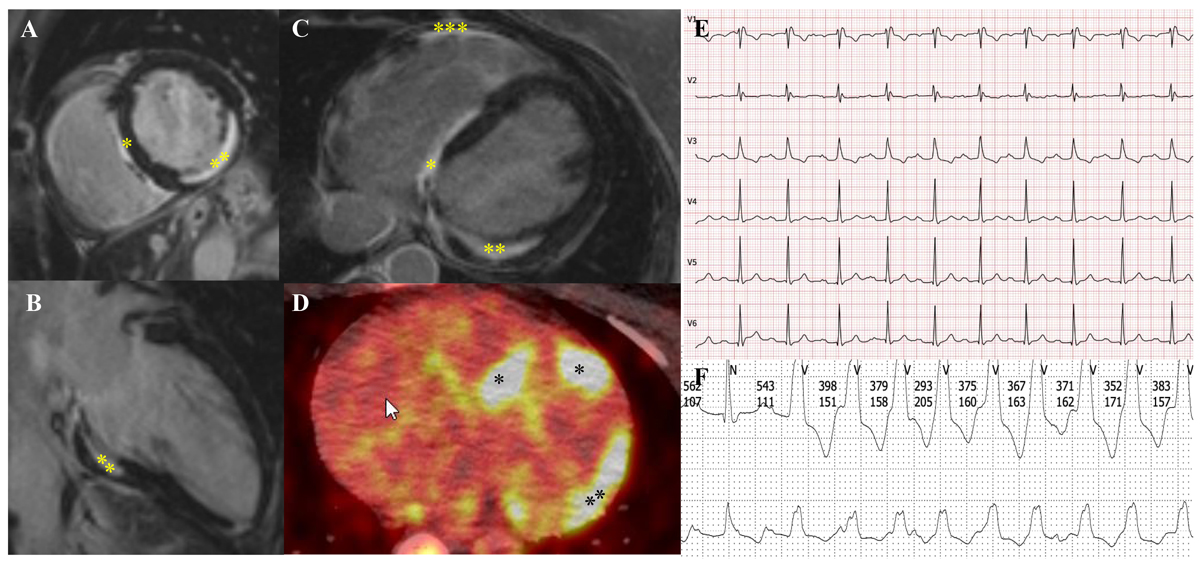

Cardiac sarcoidosis is a rare but potentially life-threatening manifestation, which is observed in 2–7% of sarcoidosis patients and in up to 83% of cases in autopsy series [68–72]. Thus, it is assumed that a significant proportion of at least subclinical cardiac involvement is unrecognised. This applies also to other organs that are not routinely biopsied. According to unpublished data from several authors of this article (DF, JN, AK, JDS), a high prevalence of cardiac involvement (approximately 50%) can be observed in highly specialised sarcoidosis clinics, where modern imaging technologies may lead to detection of early cases and increased diagnostic yield in general. Cardiac involvement can result in ventricular arrhythmias, high-degree heart blocks or progressive heart failure due to myocardial granulomatous infiltration and/or fibrosis at a later stage of the disease (fig. 3). Symptoms include chest pain, palpitations, dizziness and syncope. As sudden cardiac death can occur in up to 25% of patients with cardiac sarcoidosis, an early diagnosis and appropriate treatment is crucial [73].

Figure 3 51-year-old woman with sarcoidosis and cardiac involvement. A–C demonstrates myocardial fibrosis in the interventricular septum (*), inferolateral wall (**) and the right ventricle (***) on cardiac magnetic resonance imaging. D shows the corresponding cardiac FDG-PET/CT with mild inflammation of the septum (*) and the lateral wall (**). E: Her ECG shows a compromised conduction system with first degree atrioventricular block (PQ time 264 ms) and complete right bundle branch block. F: She had repeated nonsustained ventricular tachycardia on Holter monitor. With consideration of all findings together, she was recommended to undergo insertion of a two-chamber intracardiac cardioverter defibrillator for primary prophylaxis of sudden cardiac death (courtesy Dr C. Gruner, USZ).